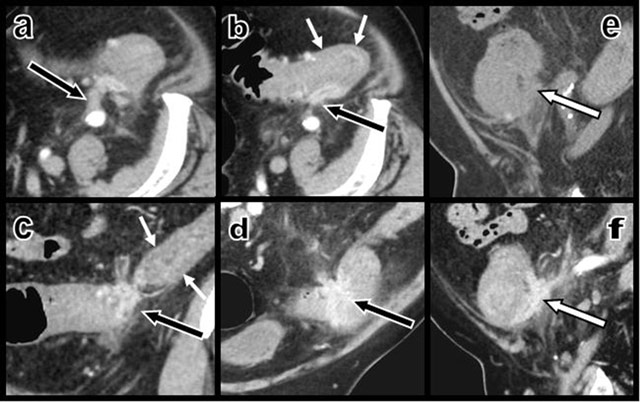

Figure 2

Contrast-enhanced axial CT views (a and b) and coronal oblique (c and d) multiplanar reconstructions (MPR) show a contrast-enhancing “scar-like” structure (black arrows) infiltrating the thickened colonic wall – due to a hypertrophy of the muscular layers (small white arrows) as confirmed by ultrasound – at the level of the sigmoid and descending colonic junction. This retracting tissue develops multiple adherences with the retroperitoneum. Sagital MPR views before (e) and after (f) intravenous iodine contrast injections illustrate the sharp enhancement of the curvilinear retractile “scar” (white arrow) that infiltrates the colonic wall and staples the colon on the retroperitoneum.